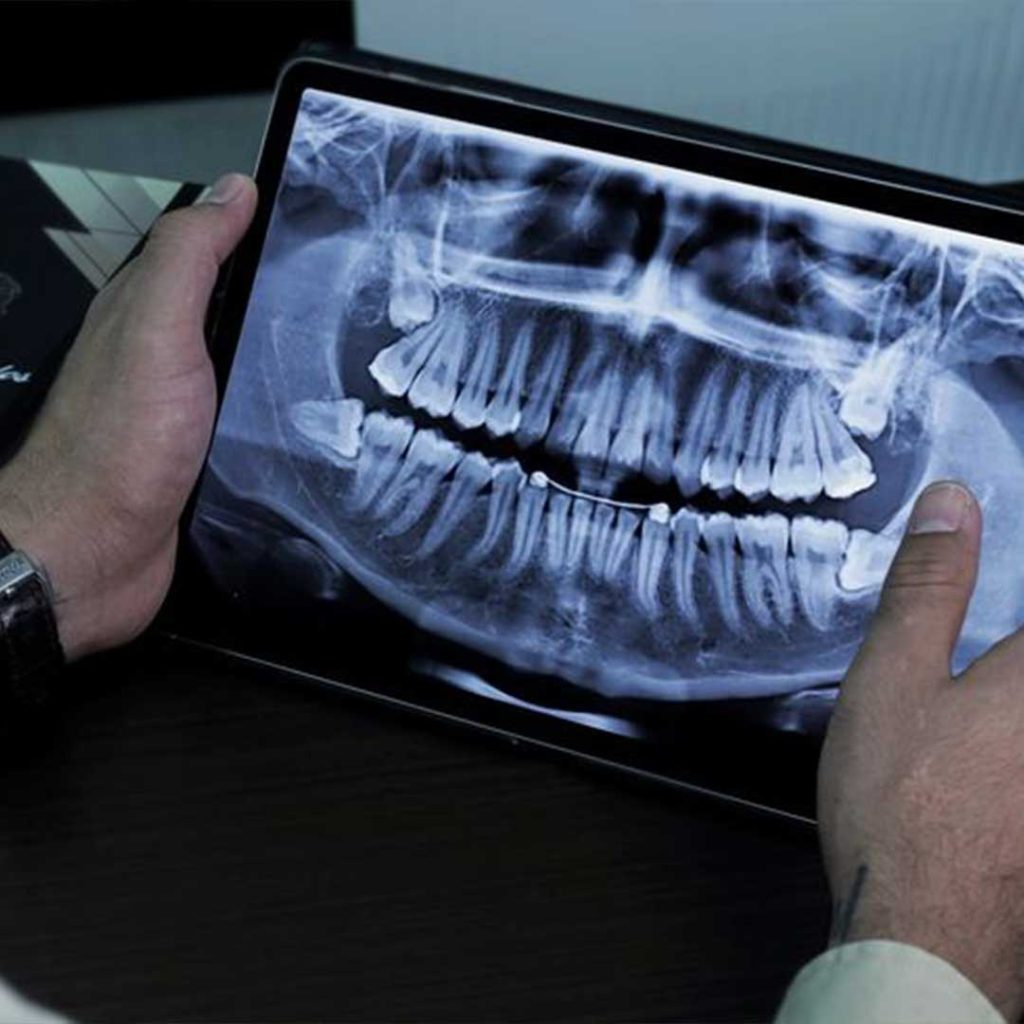

Oral Surgery & Dental Implant Specialists of San Diego

Oral surgery & dental implant specialists of San Diego? Discover the expert care, 3D technology, and patient-first approach at Elevated Oral Surgery.